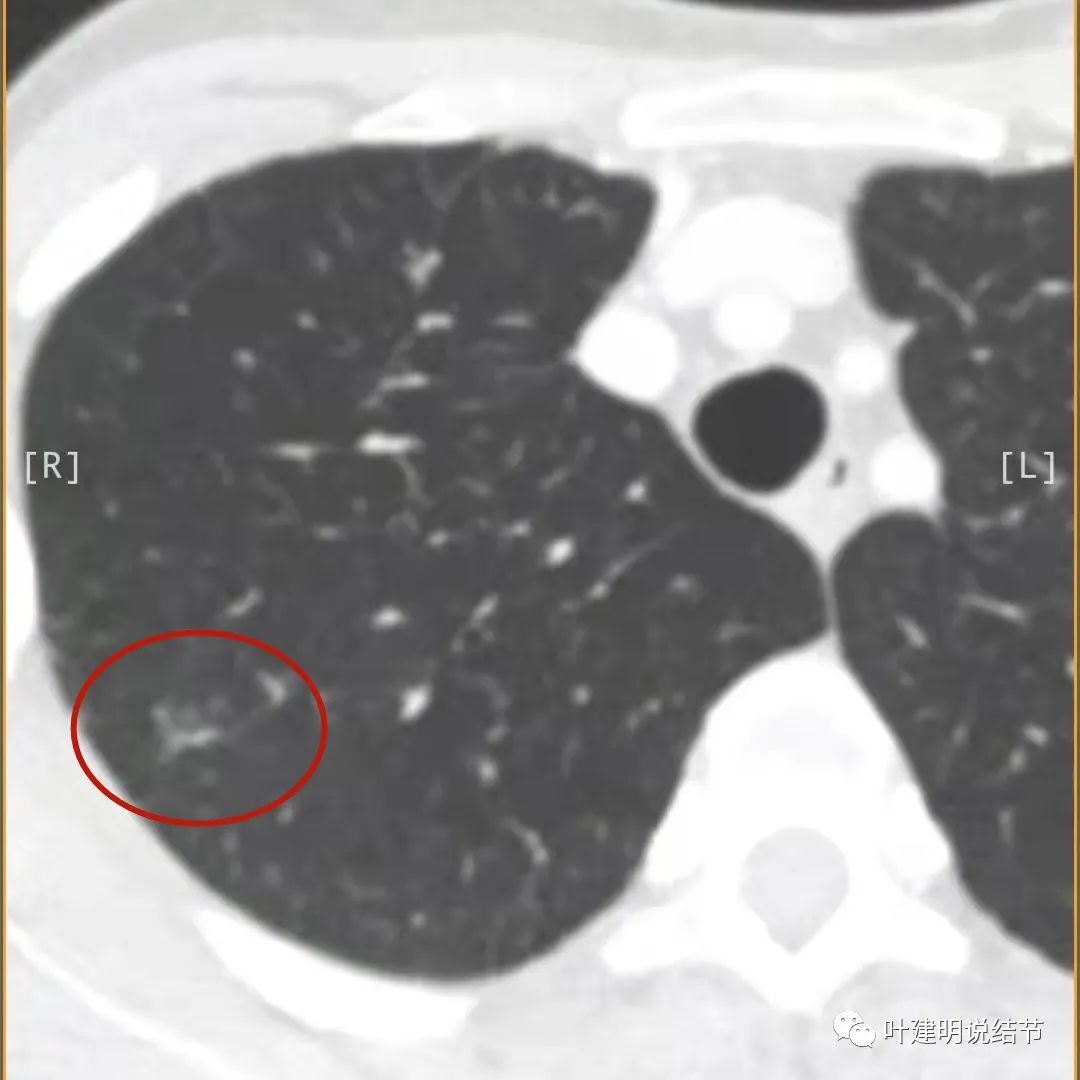

病灶出现,模糊的磨玻璃影

部分密度过高,且呈条状

邻近胸膜有增厚(蓝色箭头),主病灶边界较清(红色箭头),实性部分密度过高(粉色箭头),旁边有磨玻璃影,散且模糊(砖色箭头)

邻近胸膜有增厚(蓝色箭头),主病灶实性部分密度过高(粉色箭头),旁边有磨玻璃影,散且模糊(砖色箭头)

邻近胸膜有增厚(蓝色箭头),主病灶实性部分密度过高(粉色箭头),旁边有磨玻璃影,散且模糊(砖色箭头),病灶有空腔(黄色箭头)

主病灶边界较清(红色箭头),实性部分密度过高(粉色箭头),病灶边缘向内凹,缺乏膨胀性(桔色箭头),病灶有空腔(黄色箭头)